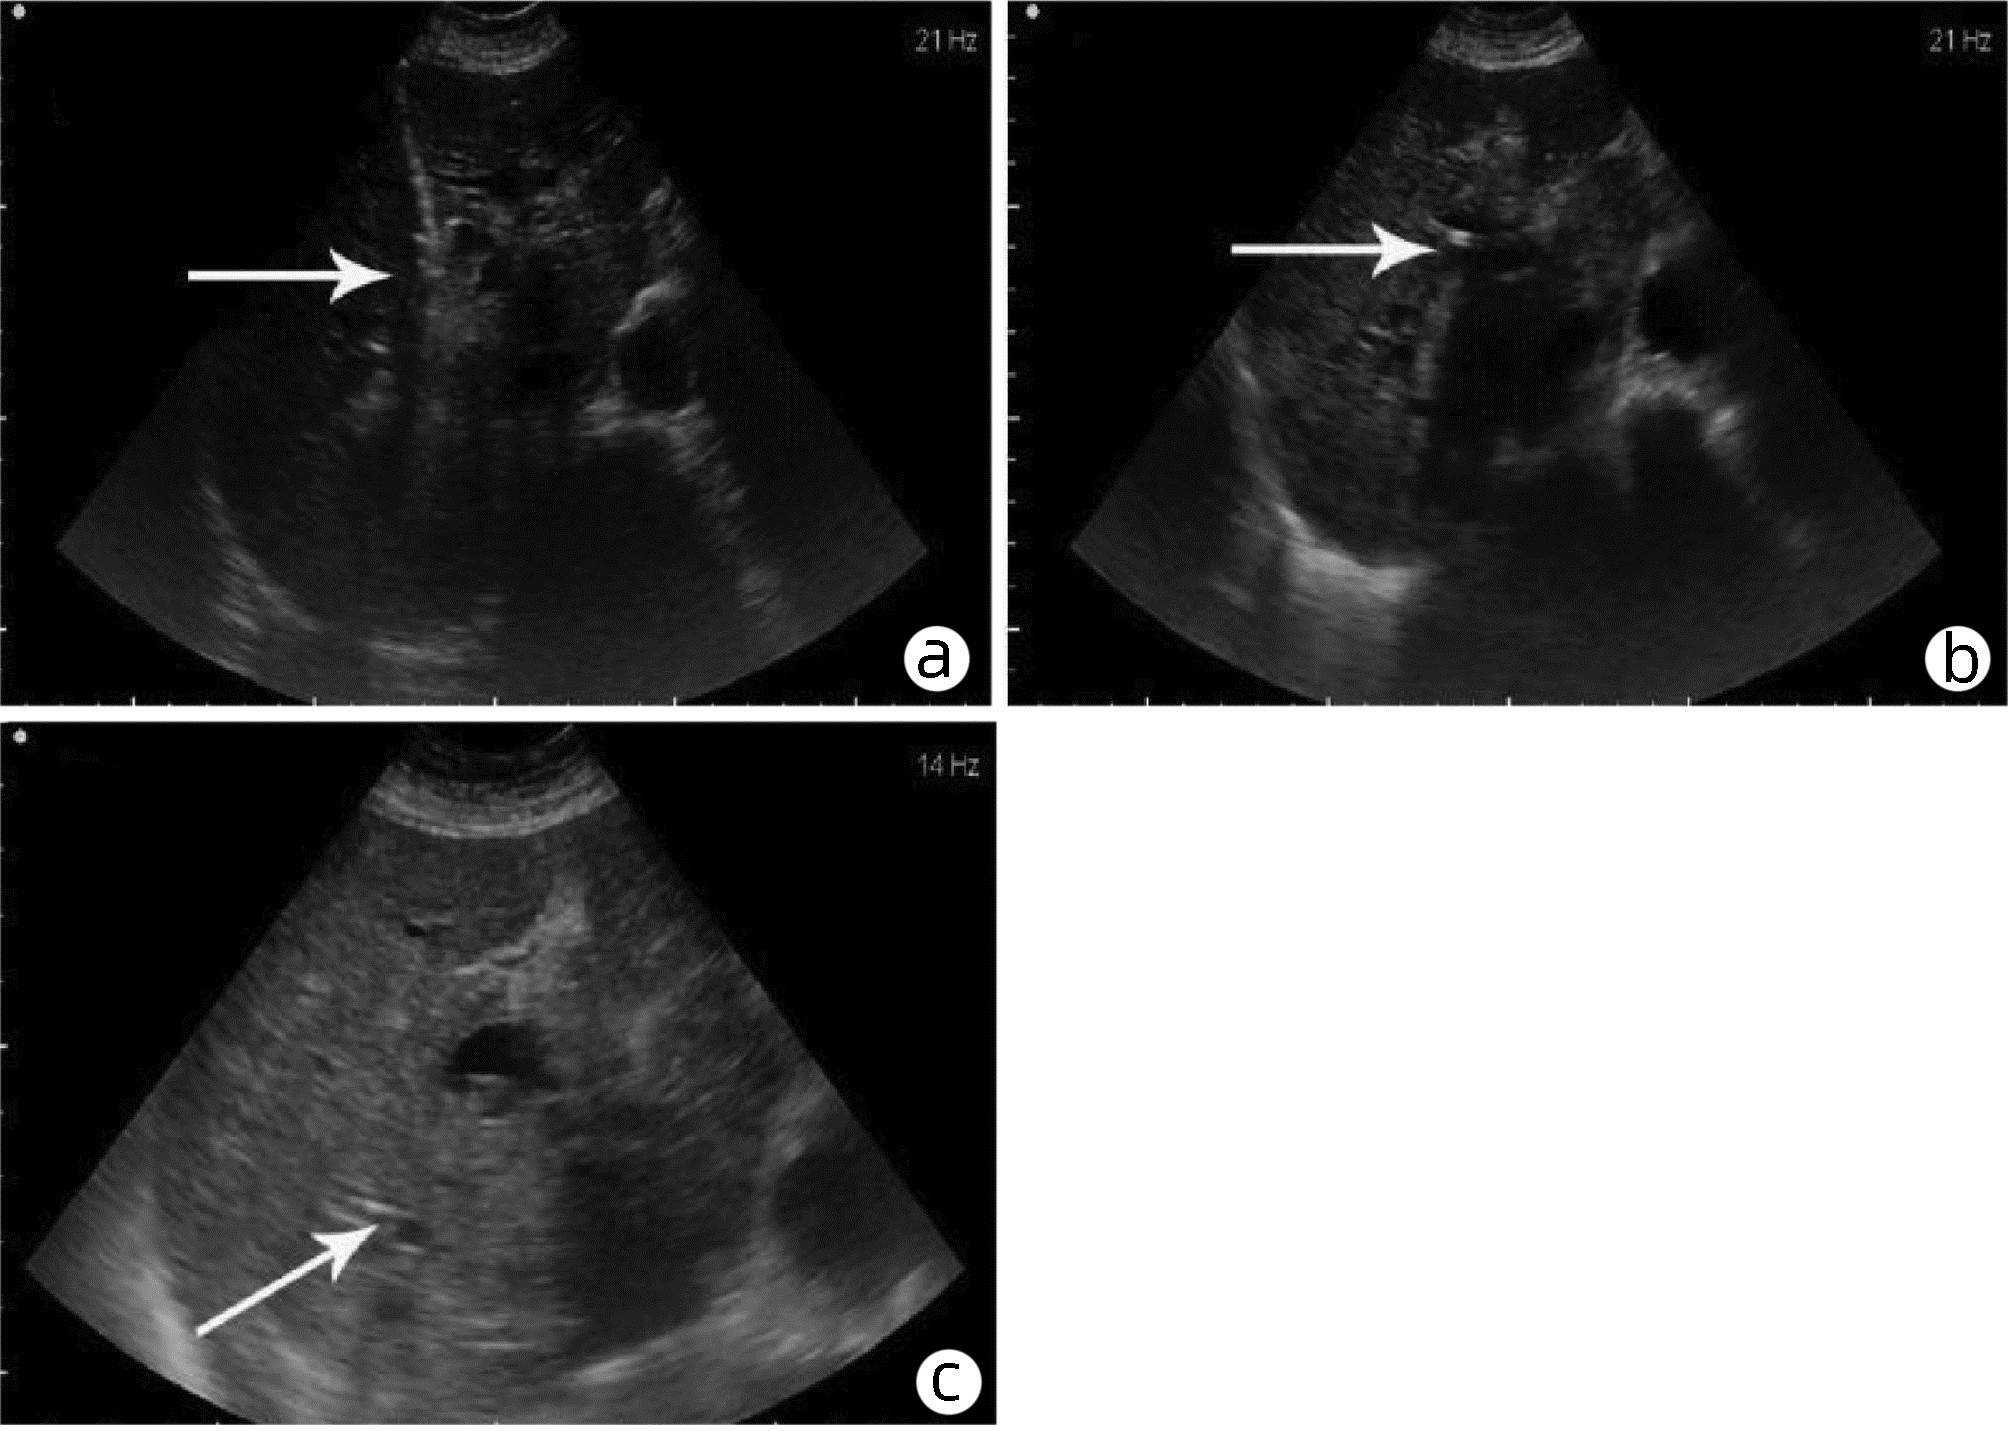

基于超声造影LI-RADS特征的肝细胞癌微血管侵犯列线图模型的构建及验证

2022, 38(11): 2520-2525. DOI: 10.3969/j.issn.1001-5256.2022.11.016

摘要(882) HTML (345) PDF (2938KB)(63)

摘要:

目的  基于肝细胞癌(HCC)患者的超声造影(CEUS)肝脏成像报告和数据系统(LI-RADS)特征建立预测微血管侵犯(MVI)的列线图模型并进行验证。  方法  选取2017年1月—2020年7月在江苏大学附属武进医院确诊的HCC患者共262例,按照1∶ 1比例随机分为建模组和验证组各131例,以术后镜下病理结果确诊MVI,其中建模组MVI 70例和验证组MVI 56例。采用超声造影评估两组的LI-RADS特征。两组间计量资料比较采用独立样本t检验;两组间计数资料比较采用χ2检验。采用单因素和多因素Logistic回归分析筛选建模组MVI的危险因素;绘制受试者工作特征曲线(ROC曲线),计算模型预测MVI的曲线下面积(AUC),评估预测准确度;应用决策曲线分析模型的一致性,比较模型预测MVI的校正曲线与标准曲线的离散度。  结果  建模组与验证组患者的临床资料和CEUS检查结果比较,差异均无统计学意义(P值均>0.05)。单因素分析显示,与MVI阴性患者相比,MVI阳性患者血清AFP水平显升高,肿瘤直径增大,LI-RADS显示LR-5“后出”和LR-M“先出”增多,LI-RADS分级较高,差异均有统计学意义(P值均<0.05)。多因素分析显示,AFP 20~400 ng/mL(OR=2.65,P<0.001)、AFP≥400 ng/mL(OR=3.98,P<0.001)、肿瘤直径≥30 mm(OR=2.12,P<0.001)和CEUS显示LR-M(OR=3.24,P<0.001) 是MVI的独立危险因素。ROC曲线显示,列线图预测建模组和验证组MVI的AUC分别为0.867和0.821。列线图模型的一致性指数C-Index为0.765(95%CI:0.701~0.834)。在建模组和验证组,列线图模型的预测校准曲线与标准曲线均接近。  结论  利用CEUS得出LI-RADS,并结合AFP和肿瘤直径建立的列线图模型有较好的应用价值,有助于指导临床术前筛选MVI高危患者,制订恰当的手术方案。